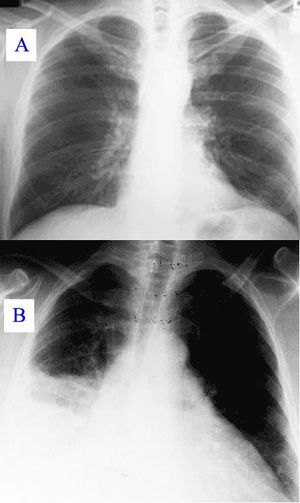

وعن طريق السماعة الطبية، يستطيع الطبيب أن يسمع أصواتًا مميزة آتية من الرئة تدل على وجود المرض. ويمكن لأشعة إكس (الأشعة السينية)، والاختبارات المعملية، أن تؤكد صحة التشخيص. أما تحديد نوع الميكروب المسبب للمرض، فإنه يتم عن طريق الاختبارات المعملية، إذ يقوم العامل الفني المتخصص بفحص عينة من بلغم المريض تحت المجهر. كما يعالج البلغم أيضًا بطرق مختلفة، حتى يمكن تنمية الكائن العضوي المُسبِّب للعدوى داخل المعمل، بحيث يمكن التعرف عليه.